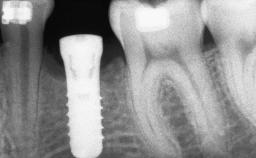

# of Implants 12

Type of Implants One-Piece|Reduced-Diameter

Placement Protocol Early or late implant placement

Bone Volume Deficient horizontally, requiring prior grafting